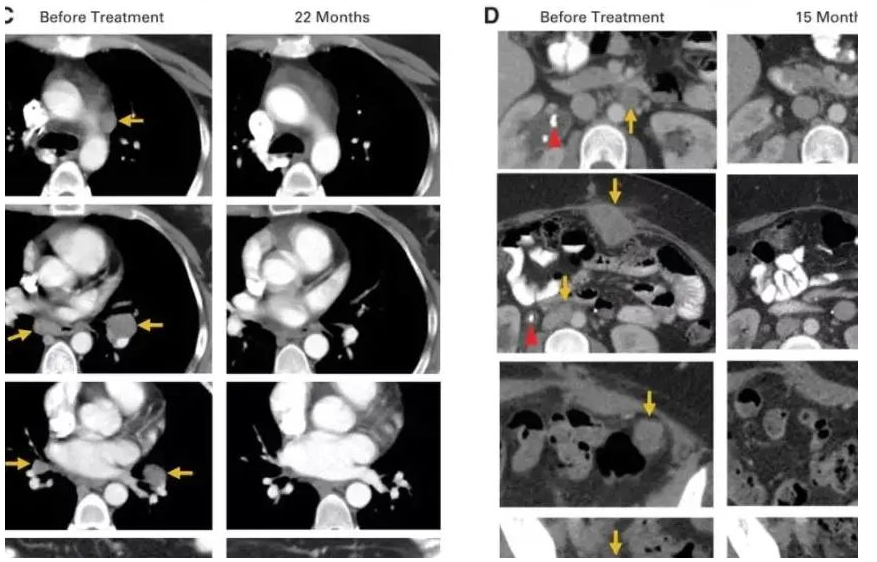

2018年,美国研究人员宣布,成功利用免疫疗法彻底治愈一名宫颈癌患者,且已5年未复发,这也是世界范围内首例使用免疫疗法治愈宫颈癌的案例。

该名被治愈的宫颈癌患者Sue Scott,当时36岁,经过多轮化疗、放疗和手术治疗,依然没有阻止癌细胞扩散,迅速侵入她的肝脏和结肠,并挤压她的输尿管。

随后,Scott参加了一项由美国国家卫生研究院临床中心(世界上从事生命科学研究最重要的研究机构之一)组织的免疫治疗治疗试验,在该实验中,医生通过手术切除她的部分肿瘤,并且分离出免疫T细胞,然后研究人员将这些肿瘤浸润淋巴细胞(TIL)进行改造和扩增并重新注入体内,形成一支免疫大军,靶向攻击癌细胞,最终成功将癌细胞“干掉”。

一个月后,她的复查结果显示:肿瘤明显缩小了。特别是腹部凸起的肿瘤已经不见了!

治疗两个月后,Scott的复查结果再次震惊了所有人,包括她自己,影像学检查显示,她的体内已经没有任何癌症的迹象。Scott开心的笑了,又哭了,她觉得这是几年来自己第一次畅快的呼吸。

2015年5月,Hinrichs博士第一次将他参与的这项临床试验的初期结果在肿瘤会议上公布,9名患者中的2名-Scott和AriccaWallace女士的转移性肿瘤全部消失了,完全缓解时间已超过两年。

2018年3月,她庆祝了癌症康复5周年,医生告诉她,她的癌症已经完全治愈。